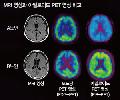

¡°10³â Èĸé Ä¡¸Å¿¹¹æÁÖ»ç ³ª¿Â´Ù¡± Áö±Ý ´Ü°è¿¡¼± Ä¡·á ¿©±â±îÁö...

¼¿ï´ëº´¿ø Á¤½Å°Ç°ÀÇÇаú À̵¿¿µ ±³¼ö´Â Ä¡¸Å ¸íÀÇ(Ù£ì¢)·Î À¯¸íÇÏ´Ù. ÀÌ ±³¼ö´Â ¶ÇÇÑ ¿ì¸®³ª¶óÀÇ Ä¡¸Å ¿¬±¸ »ç¾÷À» Ã¥ÀÓÁö°í ÀÖ´Â ¿¬±¸ÀÚÀ̱⵵ ÇÏ´Ù. Áö³ 1¿ù 17ÀÏ ¼¿ï´ëº´¿ø º»°ü 6Ãþ¿¡ ÀÖ´Â ±×ÀÇ ¿¬±¸½Ç¿¡ µé¾î¼¹À» ¶§ ÀÌ ±³¼ö´Â µ¥½ºÅ©Åé ÄÄÇ»ÅÍ ¸ð´ÏÅ͸¦ º¸°í ÀÖ¾ú´Ù. ÄÄÇ»ÅÍ È¸é¿¡´Â 70´ë ³²ÀÚ µÎ ¸íÀÇ ¿µ»óÀÌ ..